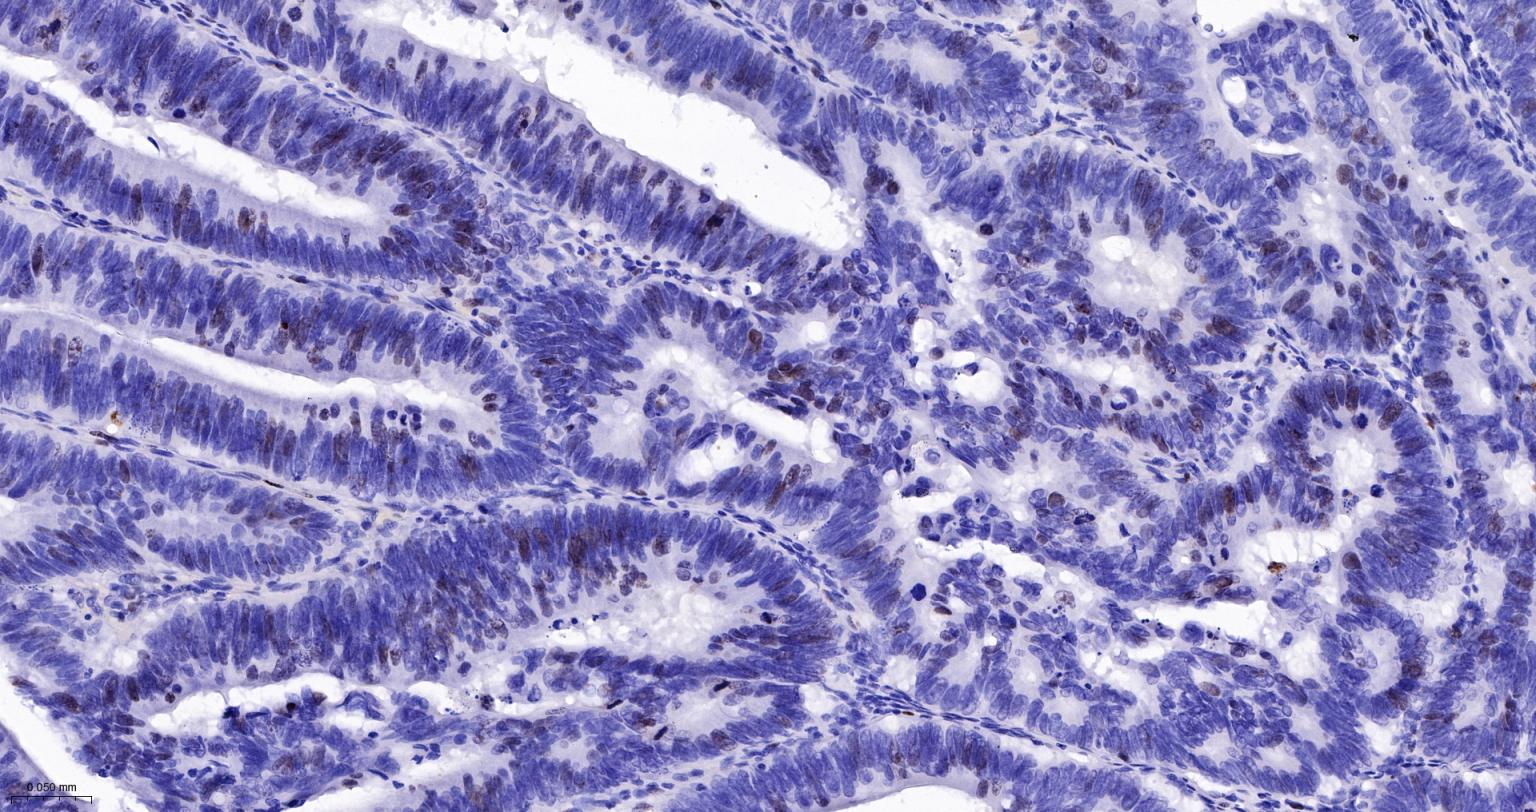

Paraformaldehyde-fixed, paraffin embedded Human Gastric Cancer; Antigen retrieval by boiling in sodium citrate buffer (pH6.0) for 15 min; Antibody incubation with Ki67Monoclonal Antibody, Unconjugated(bsm-52455R) at 1:200 overnight at 4°C, followed by conjugation to the SP Kit (Rabbit, SP-0023) and DAB (C-0010) staining.